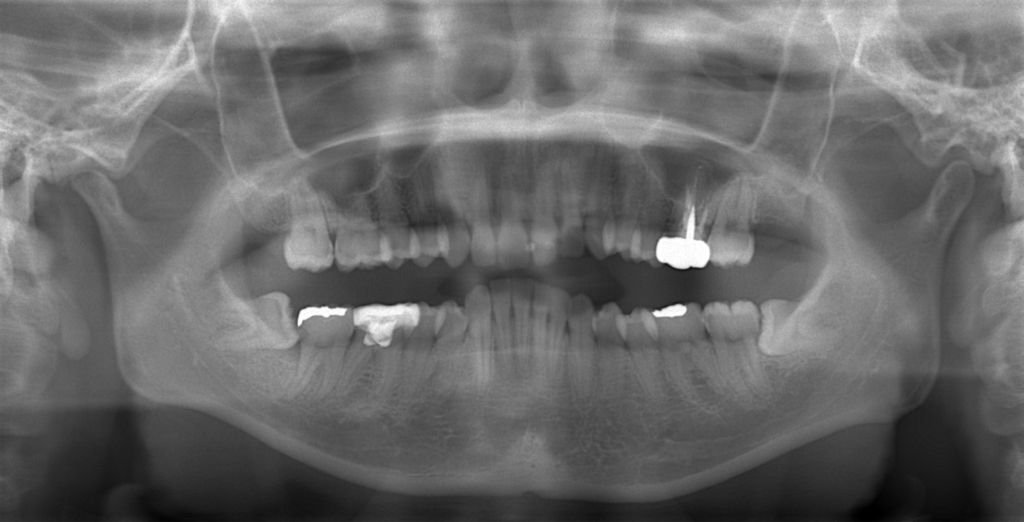

【抜歯】

上の左右の奥歯を1本ずつ計2本抜歯(前から4番目の第一小臼歯です)

下は非抜歯です

上の前歯が並んだので、ガミースマイルを改善させるために、前歯部にアンカースクリューを植立して準備を整えます。